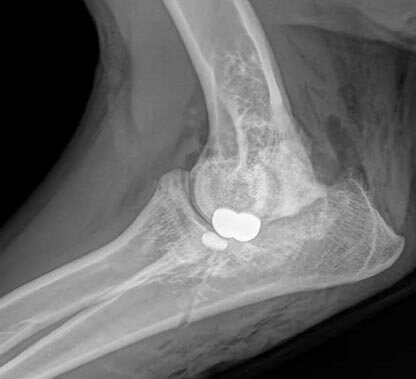

Medial Compartment Disease (MCD)—When progressive osteoarthritis from elbow dysplasia results in a complete erosion of the cartilage on the weight-bearing surfaces of the medial joint, we call it Medial Compartment Disease (MCD). In this end-stage elbow dysplasia, the medial joint collapses, and bone (humerus) grinds against bone (ulna). MCD can be diagnosed in dogs as young as 6 months old or may become apparent at any age. Limping, changes in activity levels, swollen or painful elbows, decreased performance, and behavioral changes are all clinical signs, but many of these symptoms don’t become apparent until later in the dog’s life when the osteoarthritis is severe. Replacement/resurfacing techniques can return once severely arthritic patients to their normal, pain-free activity levels.

Canine Unicompartmental Elbow (CUE) Resurfacing—Oral medications, joint injections, and physical therapy may be helpful in some cases for a period of time and should be discussed with your family veterinarian. When surgical intervention is deemed necessary, which is often the case, Canine Unicompartmental Elbow (CUE) resurfacing is a safe and effective option when arthroscopic treatment and nonsurgical options are no longer helping. During the procedure, we use a CUE implant to relieve the bone-on-bone grinding in the medial compartment while preserving the dog’s good cartilage in the lateral compartment, resulting in reduced (or eliminated) pain and lameness.